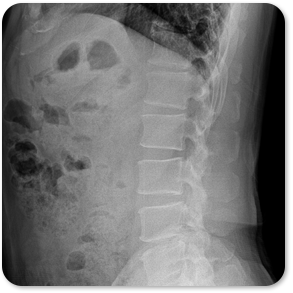

척추관 협착증은 추간판의 팽륜, 후관절과 황색인대의 비후 등의 요인으로 척추관이 좁아지면서 허리 통증, 다리 통증, 파행(오래 걷지 못하고 쉬게 됨) 등의 증상이 나타나는 질환입니다. 척추관의 협착이 심한 경우 수술적 치료가 필요하지만 수술을 받은 후에도 불편감을 호소하는 환자분들이 많습니다. 따라서 최대한 보존적 치료를 시도해보면서 경과 관찰을 하는 것이 필요합니다.

협착증 원인

수핵과 섬유륜의 퇴행성 변화

후관절, 황색인대의 변성

척추전방전위증